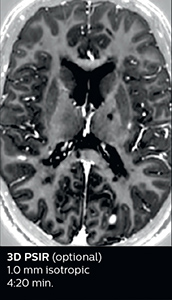

The abbreviated MS protocol for brain is only around 9 minutes, so in case of suspected multiple sclerosis, one or two more advanced sequences may be added, such as PSIR (phase sensitive inversion recovery) or susceptibility-weighted sequences to help us make more confident diagnoses in these inflammatory cases.

“We used to have long examination times for certain types of patients, a few lasting more than 40 minutes,” says Dr. Savatovsky. “What is remarkable, is that now all these examinations are below 30 minutes, which opens up opportunity to add more sequences when needed. It’s really hard to keep a patient for more than 40 minutes in the scanner, but because we have now cut scan times by at least 10 minutes, we can add more sequences without making the exam too long. And this is where the new system helps us make a difference. Examples include our examinations for informing brain tumor classification or giant cell arteritis workup, or for intracranial wall imaging – so in patients where we need several advanced sequences or high resolution sequences.” “We added three additional sequences in our brain neoplasm classification exam: a 3D SWI sequence, APT and ASL on top of 3D morphologic sequences, an isotropic DSC (dynamic susceptibility contrast) and multivoxel spectroscopy. I think that in patients that need a classification for brain mass, for example, we can provide a more detailed and confident diagnosis than before, allowing the clinicians to decide for either a medical workup if no tumor is suspected, or for neurosurgery as soon as possible if a neoplasm is suspected.” “In multiple sclerosis patients, we increasingly include a multishot susceptibility sequence [3] in our routine cases, thanks to the shorter scan times. Our abbreviated MS protocol for brain is around 8 to 9 minutes, so we can ask for one or two additional sequences to visualize the central veins, or to get an additional contrast to better depict posterior fossa lesions. In cases of white matter lesions of unknown significance on FLAIR images, for example when we see high signal hyperintensities in the brain, we can add on more advanced sequences such as PSIR (phase sensitive inversion recovery) or susceptibility-weighted sequences to help us in distinguishing between MS and nonspecific or vascular abnormalities in these inflammatory cases.”

Looking for inflammatory lesions of the spinal cord is usually challenging with MRI, says Dr. Savatovsky. “We solved some of the challenges by implementing sequences such as 3D PSIR, which allows us to see far more lesions than the usual T2 imaging. We are starting to see cases where the MRI images at 1.5T were normal, but then we do see lesions when performing the PSIR at 3.0T.” [1] “Elition also performs very well in imaging of the bony spine, the discs and degenerative disease, especially now that we can include at least one 3D sequence in every scan. For example, we perform a lot of 3D spin-echo (TSE) sequences when imaging degenerative lumbar spines. Thanks to Compressed SENSE and the 3D SpineVIEW protocols, we have a very high signal intensity with no flow voids, so the image quality is very good. The possibility to reformat the images in every plane raises the diagnostic confidence, especially in patients who have to undergo surgery.”